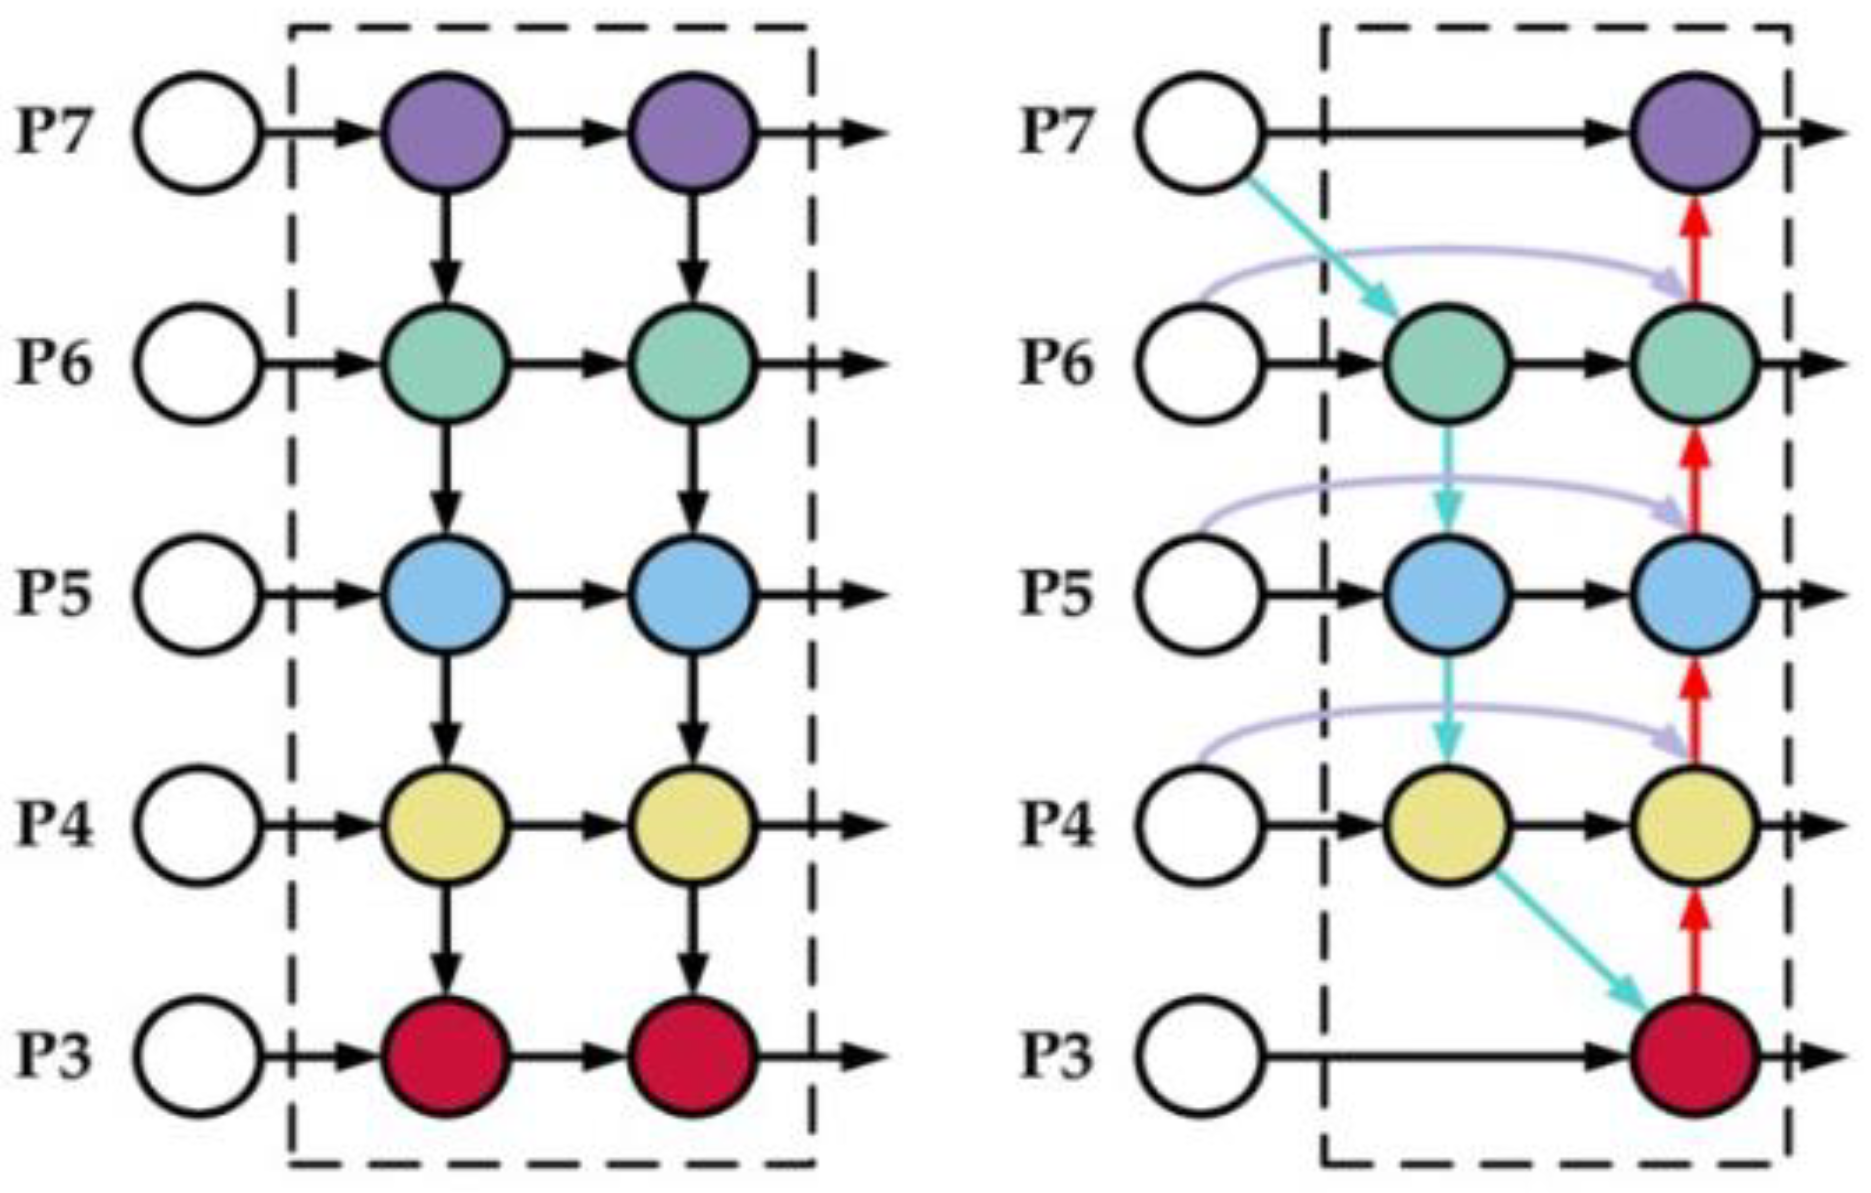

Bi-Directional Feature Pyramid Network (Bi-FPN)